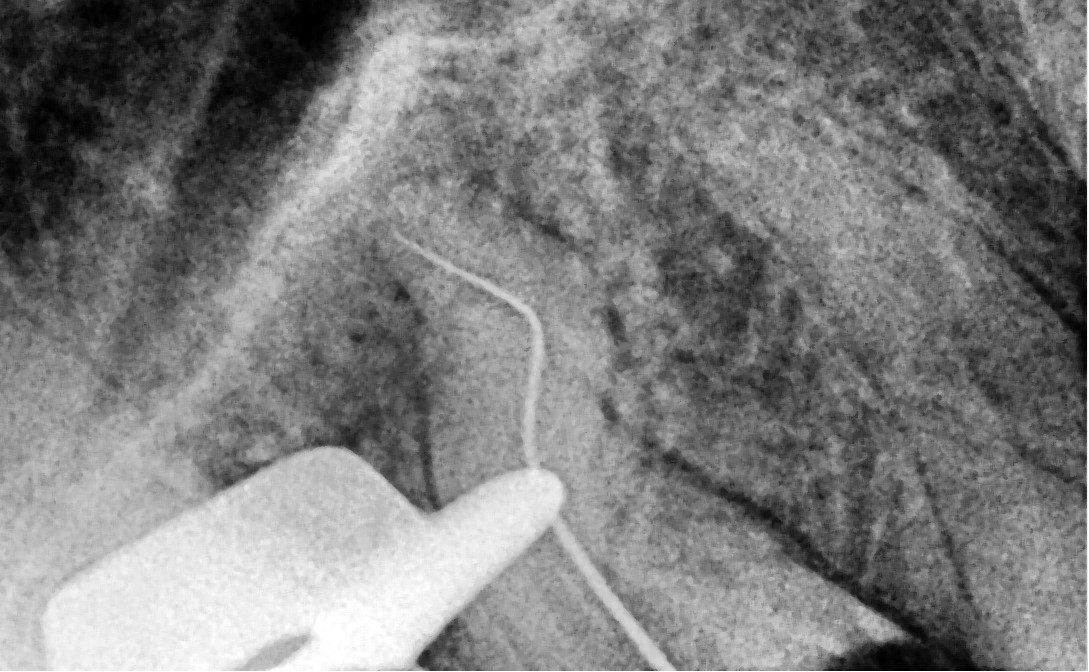

• After rubber dam isolation, treatment was initiated.

The coronal gutta-percha was removed using the SuperSystem “Retreat One” (25/06) file and the Perfect Micro H-shaper (image 2)